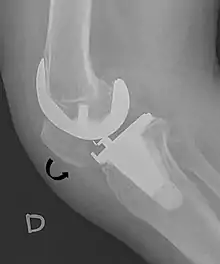

Patella baja.[4]

A patella alta is a high-riding (superiorly aligned) patella. An attenuated patella alta is an unusually small patella that develops out of and above the joint.

A patella baja is a low-riding patella. A long-standing patella baja may result in extensor dysfunction.[5]